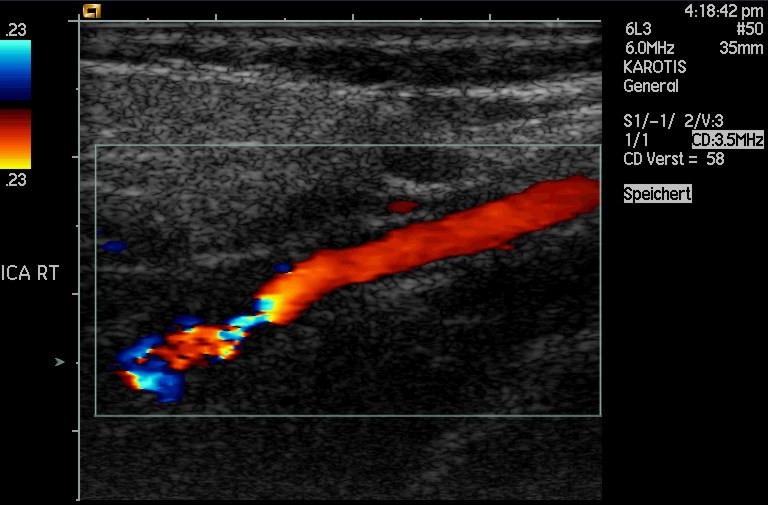

Ultrasonic waves (ultrasound) are sound waves with a frequency greater than \(\text{20 000}\) \(\text{Hz}\) (the upper limit of human hearing). These waves can be used in medicine to determine the direction of blood flow. The device, called a Doppler flow meter, sends out sound waves. The sound waves can travel through skin and tissue and will be reflected by moving objects in the body (like blood). The reflected waves return to the flow meter where its frequency (received frequency) is compared to the transmitted frequency.Because of the Doppler effect, blood that is moving towards the flow meter will change the sound to a higher frequency and blood that is moving away from the flow meter will cause a lower frequency.

Ultrasound can be used to determine whether blood is flowing in the right direction in the circulation system of unborn babies, or identify areas in the body where blood flow is restricted due to narrow veins. The use of ultrasound equipment in medicine is called sonography or ultrasonography.

Colour Doppler imaging of cervicocephalic fibromuscular dysplasia